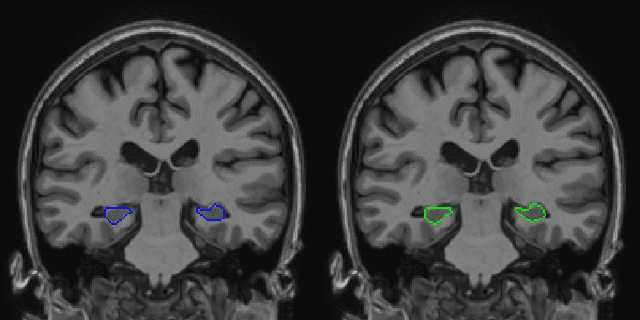

Abstract:Hippocampus segmentation on magnetic resonance imaging (MRI) is of key importance for the diagnosis, treatment decision and investigation of neuropsychiatric disorders. Automatic segmentation is a very active research field, with many recent models involving Deep Learning for such task. However, Deep Learning requires a training phase, which can introduce bias from the specific domain of the training dataset. Current state-of-the art methods train their methods on healthy or Alzheimer's disease patients from public datasets. This raises the question whether these methods are capable to recognize the Hippocampus on a very different domain. In this paper we present a state-of-the-art, open source, ready-to-use hippocampus segmentation methodology, using Deep Learning. We analyze this methodology alongside other recent Deep Learning methods, in two domains: the public HarP benchmark and an in-house Epilepsy patients dataset. Our internal dataset differs significantly from Alzheimer's and Healthy subjects scans. Some scans are from patients who have undergone hippocampal resection, due to surgical treatment of Epilepsy. We show that our method surpasses others from the literature in both the Alzheimer's and Epilepsy test datasets.

Abstract:Hippocampus segmentation plays a key role in diagnosing various brain disorders such as Alzheimer's disease, epilepsy, multiple sclerosis, cancer, depression and others. Nowadays, segmentation is still mainly performed manually by specialists. Segmentation done by experts is considered to be a gold-standard when evaluating automated methods, buts it is a time consuming and arduos task, requiring specialized personnel. In recent years, efforts have been made to achieve reliable automated segmentation. For years the best performing authomatic methods were multi atlas based with around 90\% Dice coefficient and very time consuming, but machine learning methods are recently rising with promising time and accuracy performance. A method for volumetric hippocampus segmentation is presented, based on the consensus of tri-planar U-Net inspired fully convolutional networks (FCNNs), with some modifications, including residual connections, VGG weight transfers, batch normalization and a patch extraction technique employing data from neighbor patches. A study on the impact of our modifications to the classical U-Net architecture was performed. Our method achieves cutting edge performance in our dataset, with around 96% volumetric Dice accuracy in our test data, and GPU execution time in the order of seconds per volume. Also, masks are shown to be similar to other recent state-of-the-art hippocampus segmentation methods.